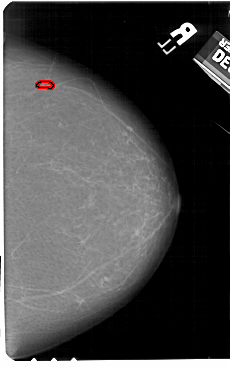

FILE: A_1601_1.RIGHT_MLO.OVERLAY

TOTAL_ABNORMALITIES 1

ABNORMALITY 1

LESION_TYPE CALCIFICATION TYPE PLEOMORPHIC DISTRIBUTION LINEAR

ASSESSMENT 4

SUBTLETY 2

PATHOLOGY BENIGN

TOTAL_OUTLINES 1

BOUNDARY